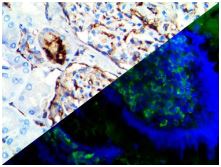

Bio SB has developed a highly sensitive Immunofluorescence and non-biotin monovalent Fab micropolymer IHC detection systems for the detection of IVD antibodies for Complement (C1q, C3c, C3d, C4c, C4d), Serum Proteins (Albumin and Fibrinogen) and Immunoglobulins (IgA, IgD, IgE, IgG, IgM, Kappa and Lambda) related to autoimmune conditions. Our innovative IF and IHC detection systems and high affinity antibodies, have opened the doors for a faster and accurate Immunofluorescence and Immunohistochemistry applicable to Autoimmune Disease like Nephropathies and Lupus.

These antibodies and detection systems are intended for use in Immunohistochemical (IHC) and Immunofluorescence (IF) applications of formalin-fixed paraffin-embedded tissues (FFPE), frozen tissue sections and cell preparations.

InDirect Immunofluorescence Detection

Rabbit FluoroDetector FITC |

Rabbit FluoroDetector FITC with FluoroMounter |

Rabbit FluoroDetector FITC with FluoroMounter with DAPI |